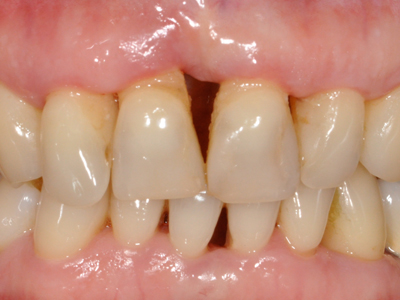

Alcuni esempi di patologie orali